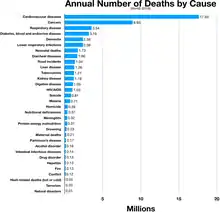

- Both influenza and coronaviruses cause respiratory tract infection that can lead to morbidity and mortality, especially in those who are immunocompromised or who have no existing immunity to the viruses. Indeed, while the COVID-19 should not be taken lightly, influenza is a much bigger problem, but because it is relatively common and has been around for a long time, it does not receive the attention that new viral outbreaks do. The COVID-19 is scary because it is new and we do not know a lot about it yet. New viruses are always scary because we have little to no protective immunity against them and we do not have vaccines. There is work going on to understand and develop preventive strategies to deal with this COVID-19 threat. However, universal precautions to limit its spread are very important right now until a new vaccine or another strategy is available.

- Jeffrey A. Woods, as quoted in “Should, and how can, exercise be done during a coronavirus outbreak? An interview with Dr. Jeffrey A. Woods”, by Weimo Zhu, J Sport Health Sci. (2020 Mar Published online 2020 Feb 4); 9(2): 105–107.